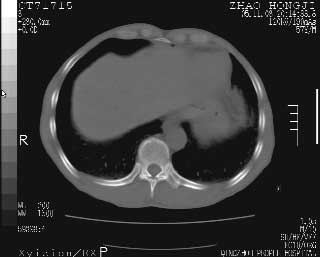

临床资料:男性,57岁,上腹部疼痛并5天,突然加重并延及全腹伴恶心5小时入院。胰淀粉酶化验在正常范围。检查:腹肌紧张,全腹压痛、反跳痛,尤以右上腹部为著。肠鸣音减低。血常规:wbc14.6x10/9, n:11.3x10/9 ,血压:135/90mmhg. 胸部透视:腹部肠腔轻度张气,未见其它异常改变。

肝右前缘少量积气,其他未见明显异常.考虑上消化道穿孔.

小网膜囊积气液,胃壁僵硬。考虑胃穿孔。

小膜网膜积液,肝缘气腹征,上消化道穿孔。

胰腺形态规则,胰周脂肪间隙清晰,结合临床可排除急性胰腺炎

从图提示我同意空腔脏器穿孔的诊断,来源肠道{由于病程较短,故没能见到肠系膜聚局的征象}。

肝缘见少许气体,胰尾部见少许气体包饶(蓝色圈),12指肠上部或球部邻近胆囊周边也可见少许气体影(黄色圈),并忖托出胆囊壁,12指肠远段肠道内未见明显气体(白色箭)。

肝脏前缘见少量积气、胰尾部见少许气体包饶,肾前筋膜未见增厚,临床淀粉酶不高,意见:上消化道穿孔。

消化道穿孔。12指肠球部周和胰周积气考虑12指肠穿孔可能性大。

入院3小时后行剖腹探查术,见腹腔内大量脓性混浊液约1000ml,十二指肠球部溃疡穿孔,溃疡面约2.5x2cm,穿孔直径约0.6cm。胃内容物外益,周围组织炎性水肿明显。行十二指肠穿孔修补术。术后诊断:

1、十二指肠溃疡穿孔

2、弥漫性腹膜炎

对于少量的腹腔游离气体,ct检查较普通透视有绝对的优势,它不仅可以看到肝脏前上缘的气体,而且还能够看到小网膜区的游离气体。从而可以肯定诊断。各位分析战友的很好,感谢大家的参入!